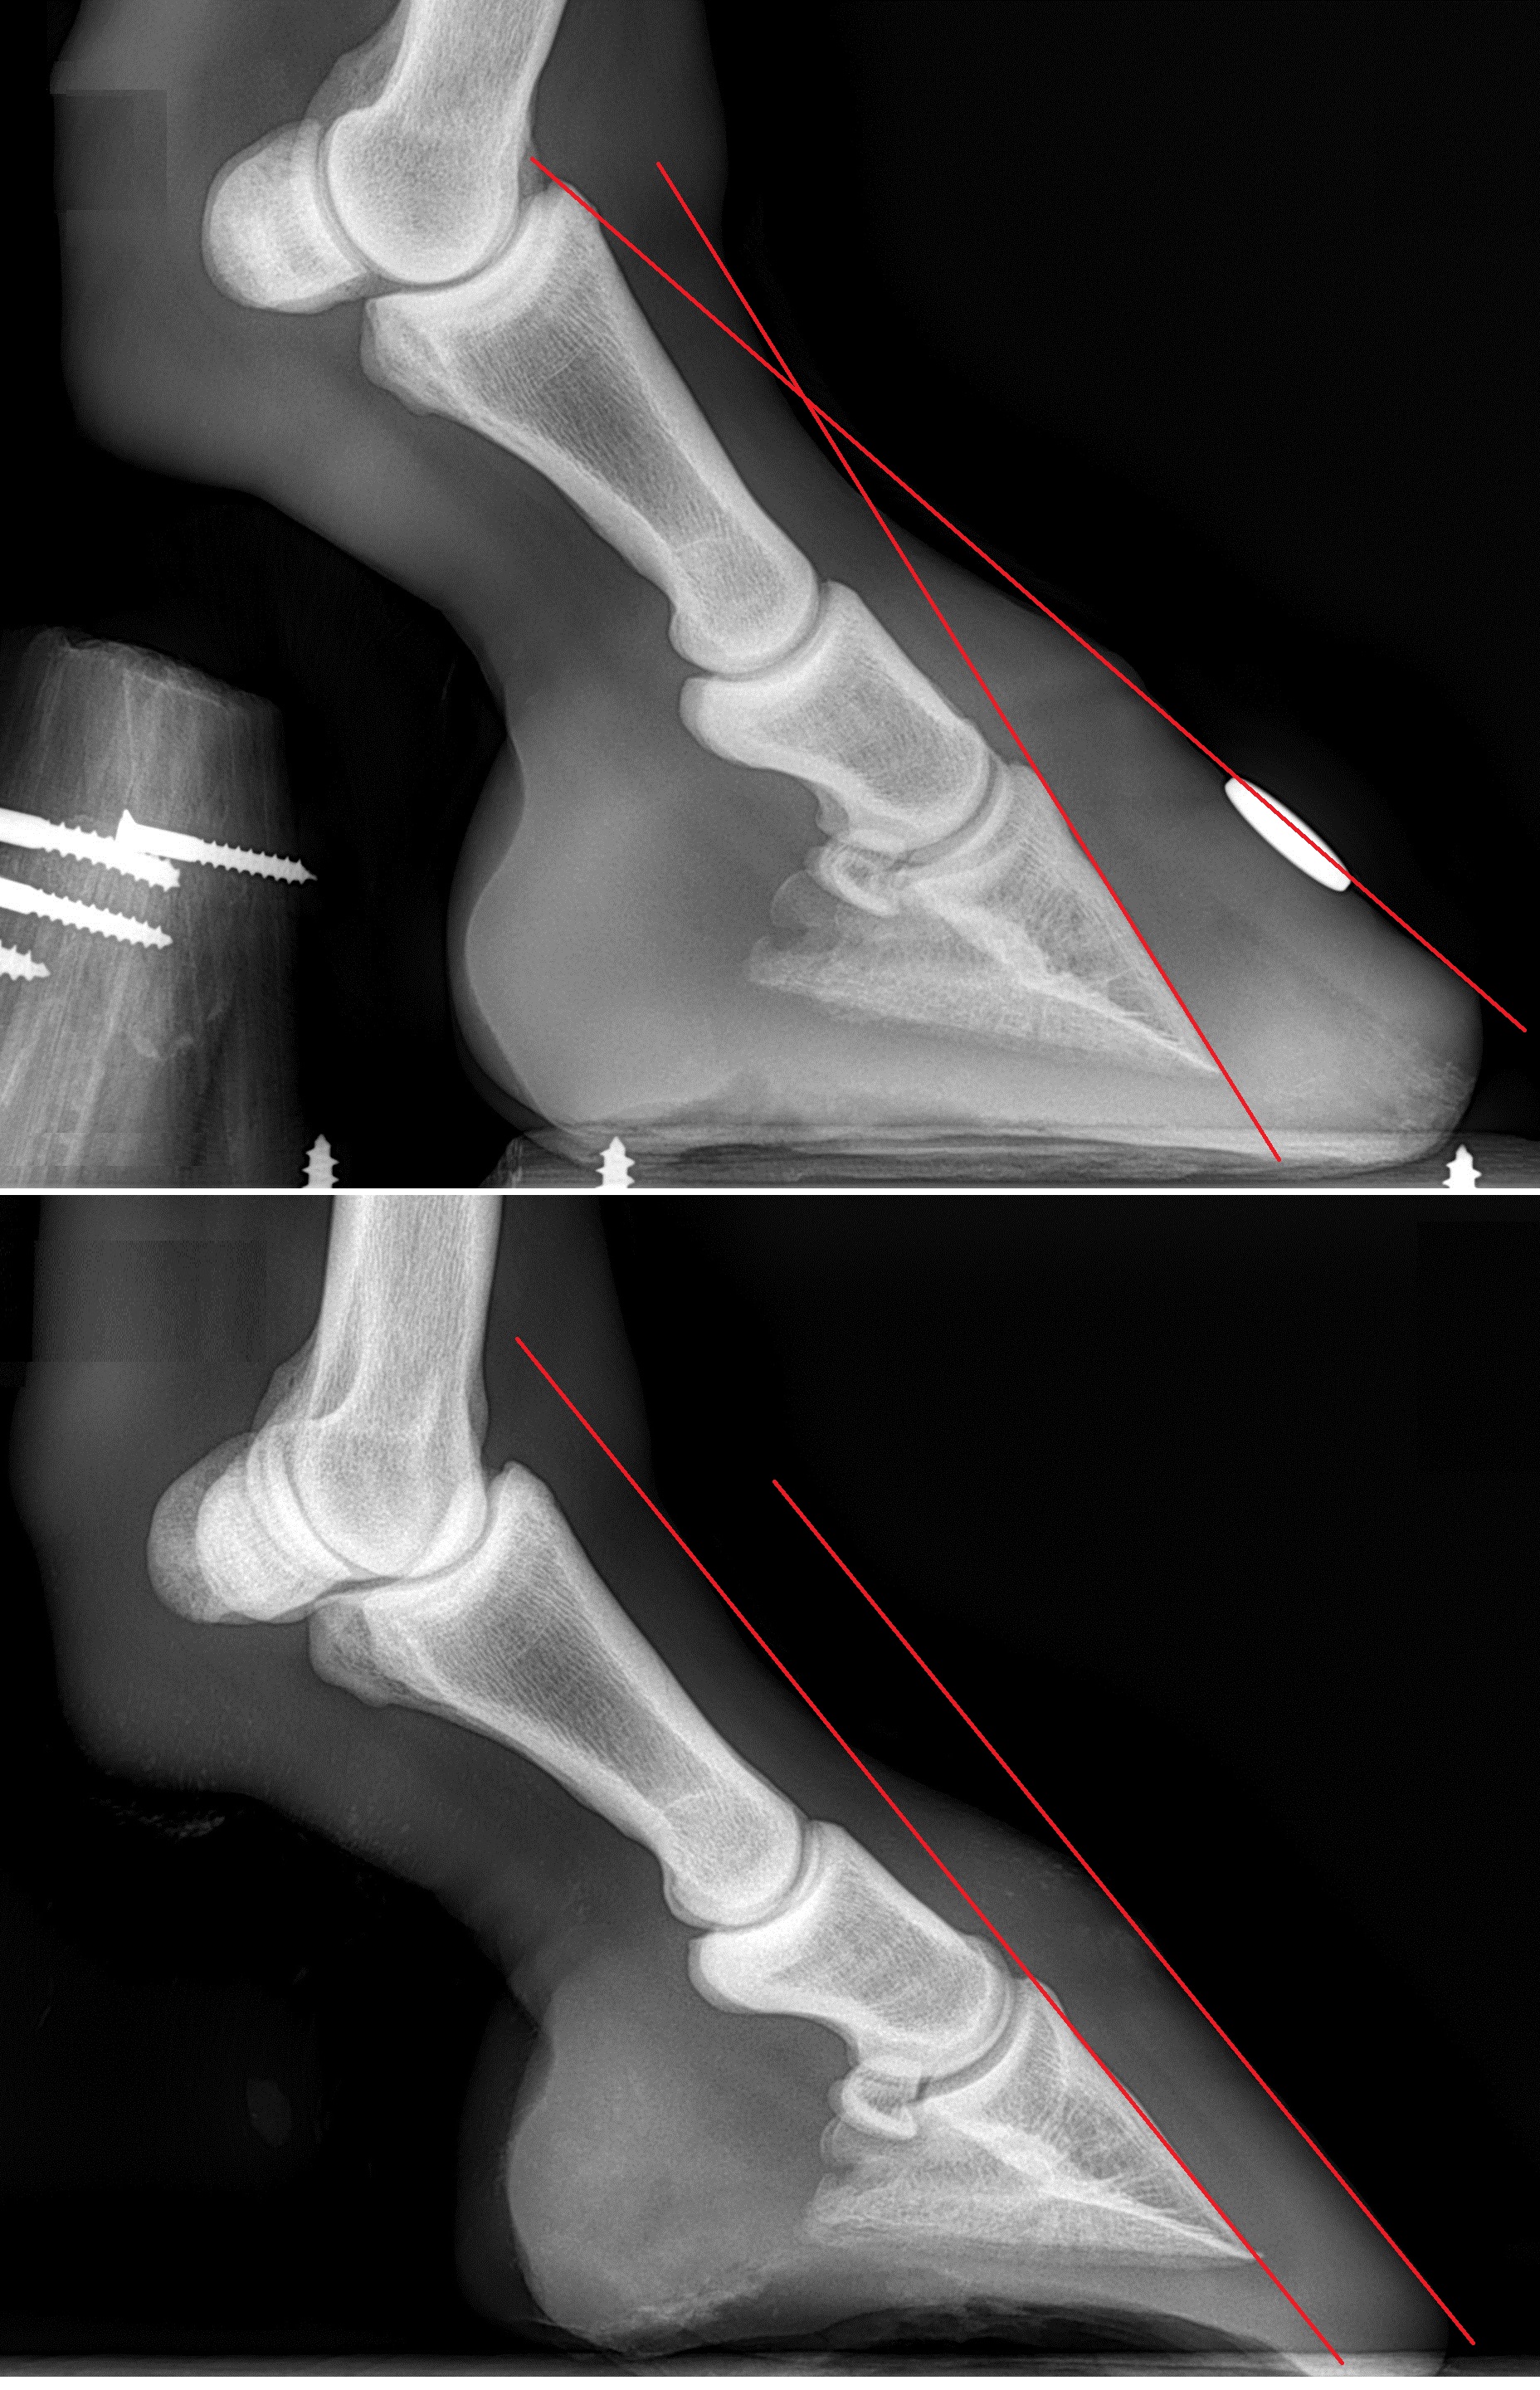

Les radios de Tristam au début de sa réhabilitation et un an plus tard.

Sur cette photo, bien que le pied ait récupéré un joli aspect, il n'est pas encore totalement guéri.

Le postérieur droit de Tristam 5 ans après le SME et la fourbure.

Grâce à une gestion adaptée, il n'a conservé aucune séquelle sur ce pied qui était pourtant le plus atteint. Il n'a jamais refait de crise et, bien qu'il ait été trop gros au moment de ces clichés, ses pieds sont restés parfaitement normaux et sains. A titre de comparaison, les photos suivantes ont été prises avant et en cours de réhabilitation :